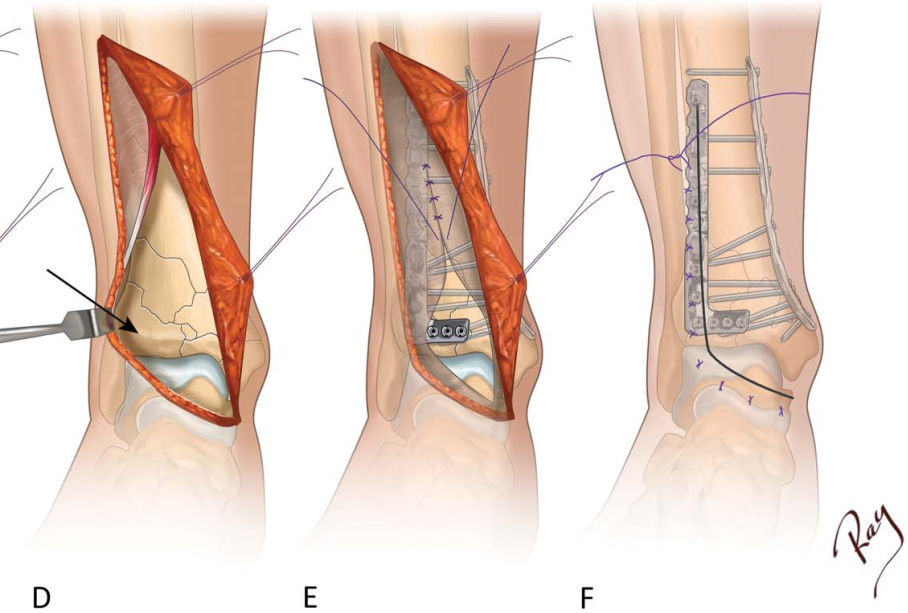

切口始于内踝尖端下方10mm 处,横向穿过踝关节至中线稍外侧,然后以110° 角(不宜更锐利)转向,沿胫骨嵴外侧10mm向近端延伸(图A),因此切口位于胫骨前肌腱外侧,其垂直部分可根据需要向近端延长。若胫骨远端外侧柱损伤更广泛,可将转折处稍向外侧移动。切口深达皮下组织,掀起全厚皮瓣,继续切开伸肌支持带,显露下方的胫骨前肌腱,切开支持带时尽量保持胫骨前肌腱在其腱鞘内不受干扰(图B)。将全厚皮瓣向内侧牵开,胫骨前肌腱向外侧牵开(图C),在踝关节水平纵向切开关节囊,显露距骨。骨膜下分离显露踝关节和骨折部位,将组织向外侧牵开,显露整个外侧关节Tillaux-Chaput骨折块(图D)。

按顺序复位关节面,通常先复位任何移位的外侧柱骨折块(Tillaux-Chaput骨折块),复位顺序为从后向前、从外到内,用克氏针临时固定关节骨折块。关节骨折块重组后,将其与近端骨折块连接。接骨板的具体放置位置取决于骨折类型,通常采用两枚接骨板,分别置于前外侧和内侧。对于近端延伸的骨折,接骨板通过开放切口置入,经皮下向近端滑动(图E),需在骨折的压缩侧(凹侧)放置一枚接骨板作为支撑。可通过触诊轻松定位接骨板的螺钉孔,经小切口植入螺钉。为填充干骺端缺损并支撑重建后的关节面,可添加自体骨移植。Pilon骨折固定后,若需要可通过该切口用小型接骨板固定腓骨。

伤口关闭顺序为:先缝合伸肌支持带和皮下组织,然后采用 Allgöwer 技术用3-0间断尼龙缝线缝合皮肤(图F)。